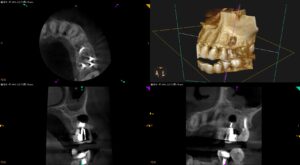

紹介患者さんの治療。 主訴は、 神経の治療をした歯が痛い… である。 歯内療法学的検査(2025.7.8) #12 Cold+2/4, Perc.(-), Palp.(-), BT(-), Perio Probe(WNL … 続きを読む 神経の治療をした歯が痛い…〜#13 Apicoectomy